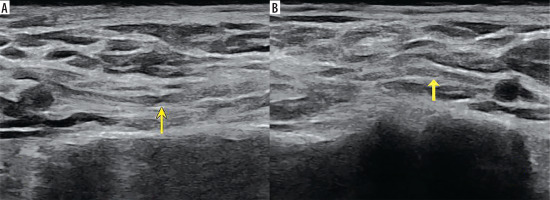

Figure 1

High-resolution ultrasound image of the suprascapular nerve torsion with a double “hourglass-like” constriction sign – marked with arrows (B) in 57-year-old patient with Parsonage-Turner syndrome in comparison with asymptomatic side (A). Images obtained by author with a 3-19 H linear probe of the Alpinion XCube90

Figure 2

High-resolution ultrasound image of LTN torsion with an ”hourglass-like” constriction sign – marked with arrow (A) with comparison to the asymptomatic side (B) in 50-year-old patient with Parsonage-Turner syndrome. Images obtained by author with a 3-19 H linear probe of the Alpinion XCube90